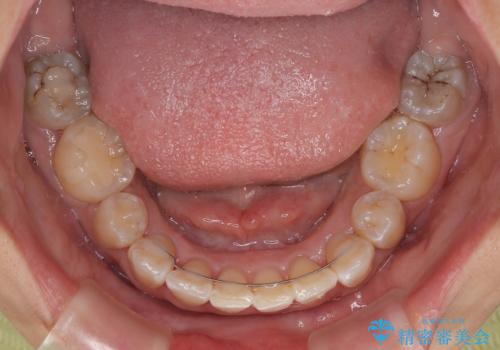

下顎は第二小臼歯を抜歯したため、治療期間が長期化すると思われましたが、大臼歯が後方に傾斜していたため、容易にスペースを閉じることができ、2年強で治療を終えることができました。

口元の突出感があるわけではなく、叢生の程度もシビアではありませんでしたが、顎骨が小さく、左右ともに最後臼歯が歯肉に埋もれているため、下顎は左右第二小臼歯を抜歯することとしました。

上顎は左右ともに残存している乳歯を抜歯し、上下歯列を整えることとしました。